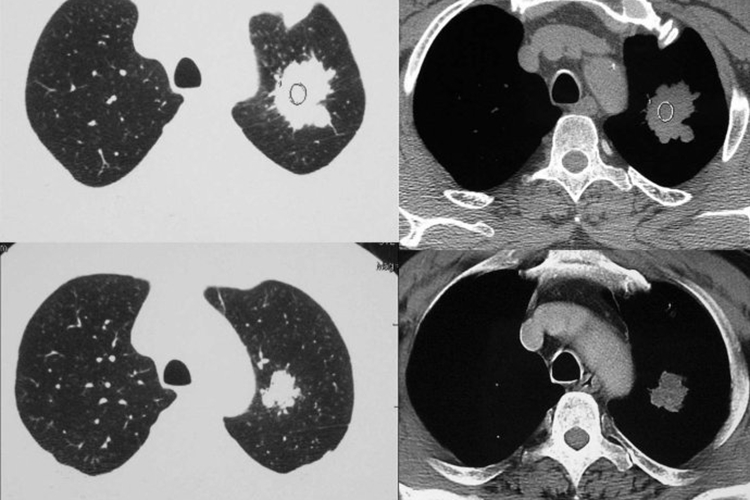

肺癌又称原发性支气管肺癌,临床常见咳嗽、血痰、胸痛、发热、气促等症状。影像学表现可分为中央型肺癌和周围型肺癌两种,具体如下:

周围型肺癌:发生在肺段以下支气管,表现为肺内结节或肿块;病灶形态不规则,呈分叶状(分叶征);边缘多发细短毛刺(毛刺征);偏心性空洞,或伴有壁结节;相邻胸膜凹陷,伴线形、喇叭口样索条影牵拉改变;增强扫描呈轻、中度不均匀强化。